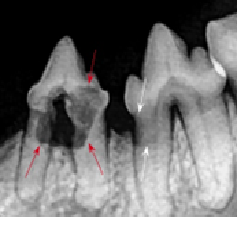

Because it is the best and safest way to care for your pet’s oral health. A dental cleaning is an unsettling experience even for a human. For your pet, it would be terrifying, and dangerous. In order to provide your pet with the best quality dental care, we must be able to look into the entire mouth, x-ray all the teeth to look for fractures and abscesses, probe the gums, scale the tartar and bacteria off of the visible tooth surfaces as well as under the gumline, and then polish all the teeth. Your pet would never allow us to do this while they are awake.

Often, when we have x-rayed the mouth and cleaned off the tartar, we find problems: fractures, loose teeth, and abscesses. Very often, these situations require that the affected teeth be extracted. If possible, we will try to do the extractions on the day of the dental cleaning. However, it is usually better for your animal to have these done as a separate procedure on another day. Either way, we will explain the situation to you and give you an estimate of costs so that you can be prepared.